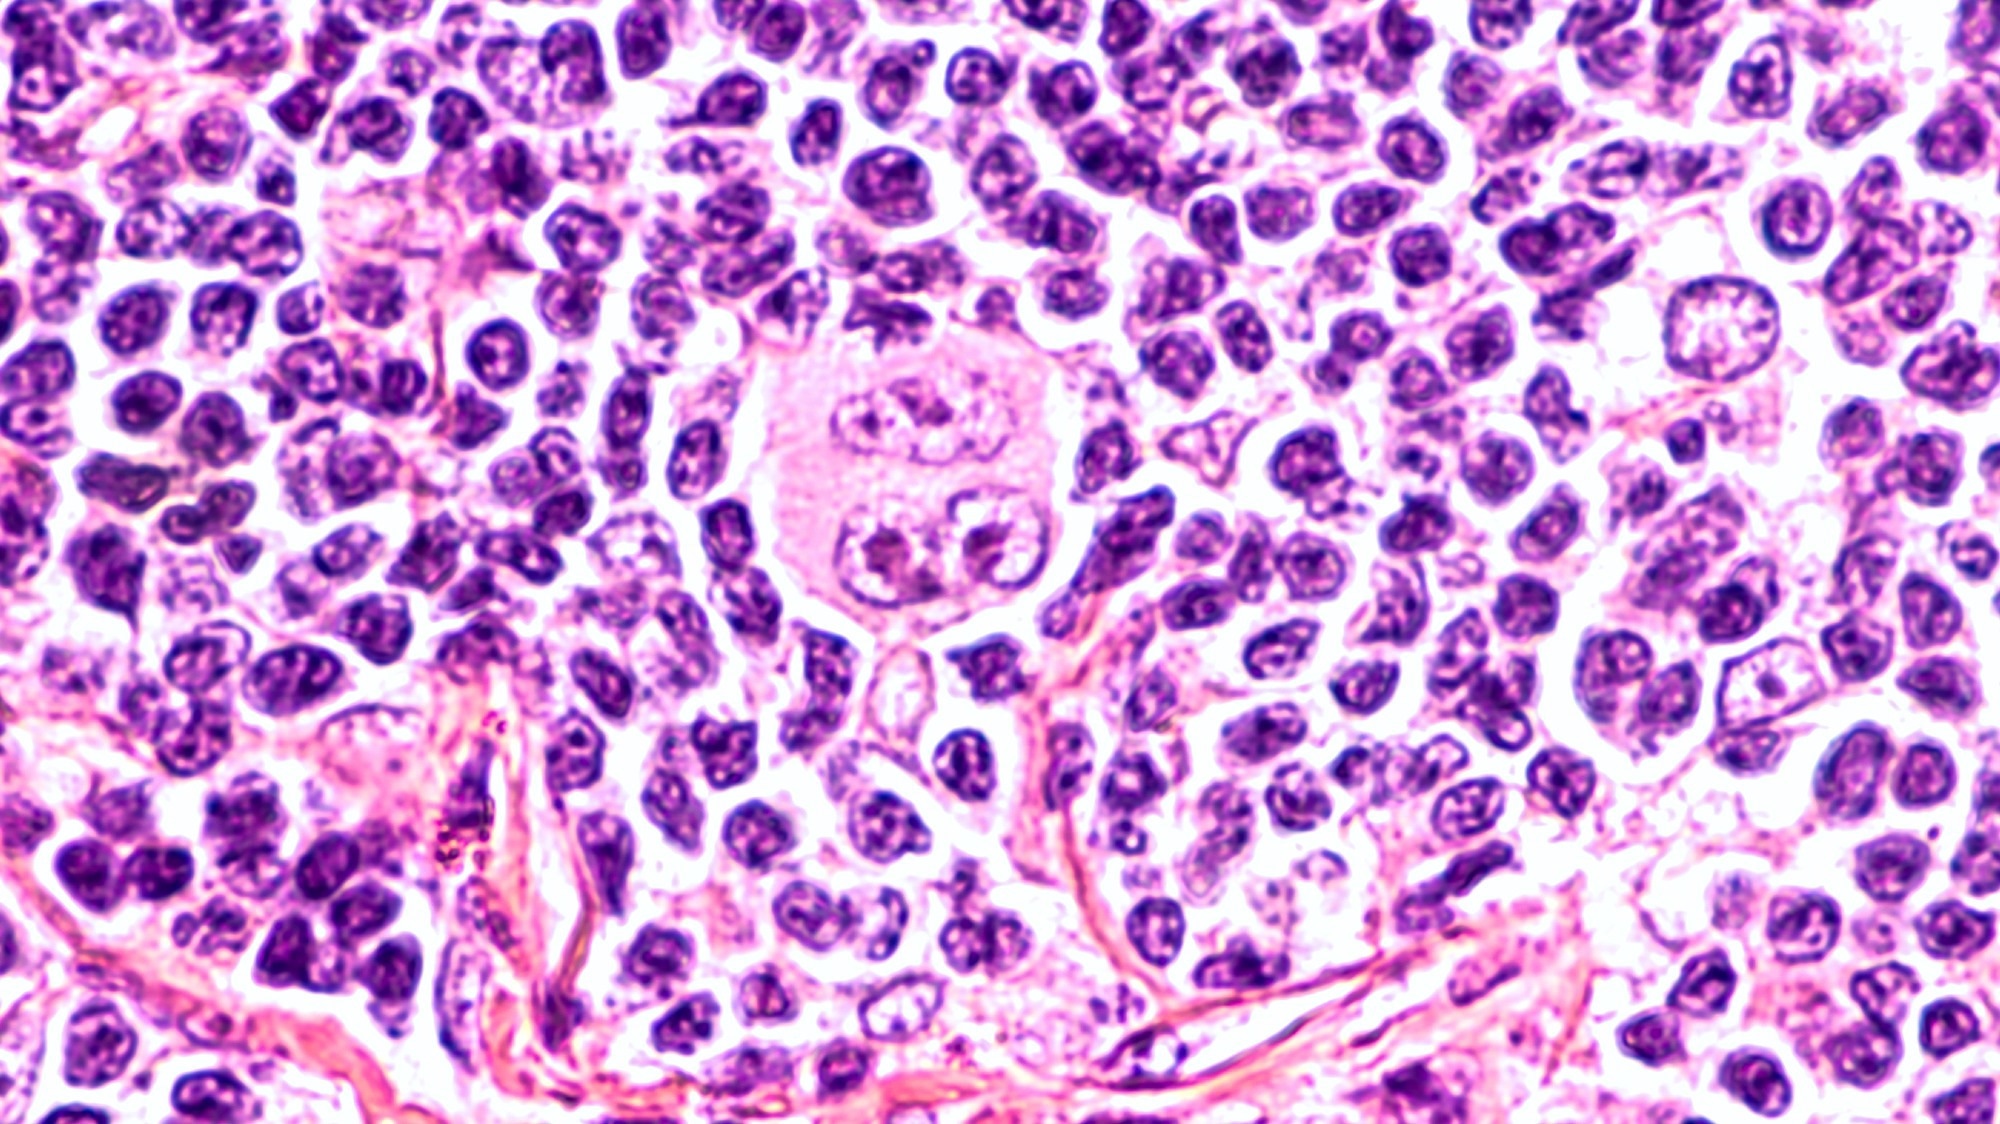

Photomicrograph of a lymph node in a patient with Hodgkin's Disease (lymphoma), showing a Reed Sternberg cell variant. Image Credit: David A Litman / Shutterstock

Photomicrograph of a lymph node in a patient with Hodgkin's Disease (lymphoma), showing a Reed Sternberg cell variant. Image Credit: David A Litman / Shutterstock

In cHL, tumor cells are primarily comprised of Reed-Sternberg (RS) cells that originate from mature B-cells. Despite this origin, RS cells typically appear much larger than B-cells due to the presence of multiple nuclei.